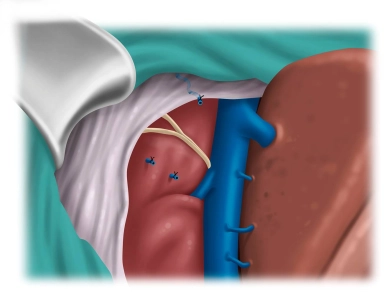

Rektovaginale Fistel: Anteriore Levatorplastik mit simultaner Sphinkterrekonstruktion